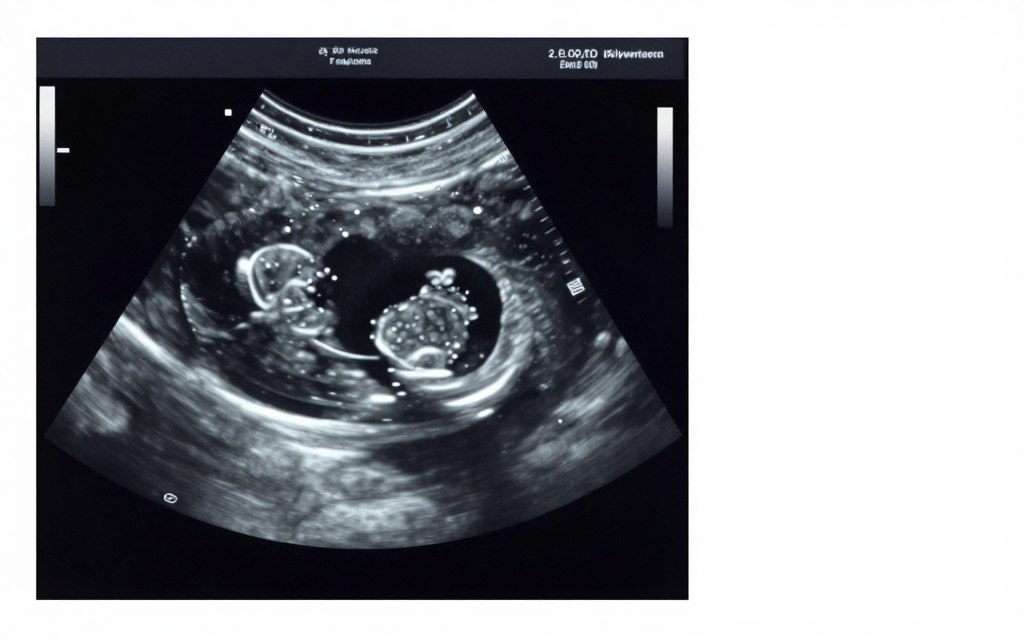

Monitoring occurs throughout stimulation through ultrasound examinations and blood tests. These procedures track follicle growth and hormone levels. When eggs reach maturity, a trigger shot initiates final egg maturation. Egg retrieval takes place approximately 36 hours after the trigger injection. This minor surgical procedure collects eggs from the ovaries using ultrasound guidance.

Fertilized eggs become embryos. Embryologists observe embryo development over several days. Day 3 embryos typically contain six to eight cells. Blastocyst embryos develop by day 5 or 6, containing over 100 cells. Many clinics prefer transferring blastocysts because they better predict successful implantation.

Around day four, the embryo becomes a morula. This solid ball of cells contains 16 to 32 blastomeres. The cells begin to differentiate and organize. A cavity forms inside the embryo. When this cavity appears, the embryo becomes a blastocyst. This typically occurs on day five or six after fertilization.

Blastocysts contain two distinct cell types. The inner cell mass will become the fetus. The trophectoderm cells will form the placenta and membranes. Blastocyst quality grading assesses expansion, inner cell mass, and trophectoderm. Higher-grade blastocysts have better implantation potential. Many clinics prefer transferring blastocysts rather than earlier-stage embryos.